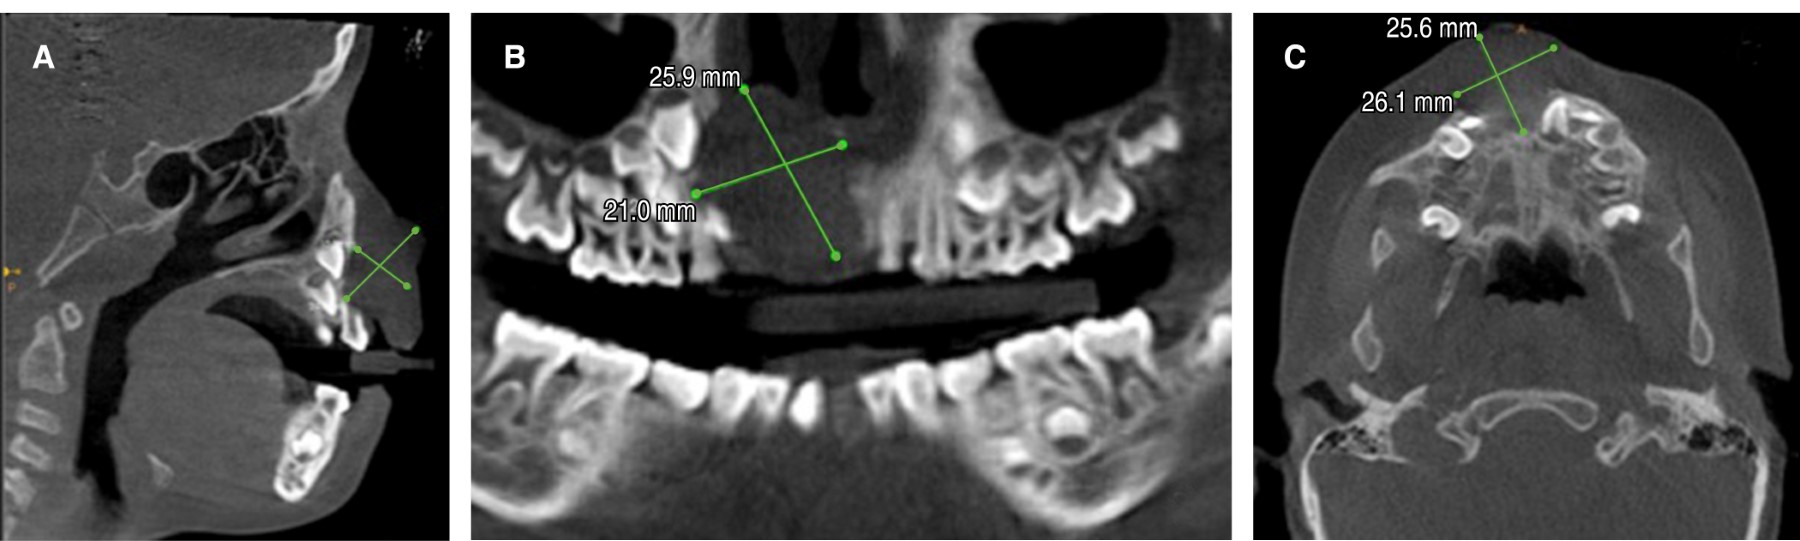

Radiográficamente, se observó un área unilocular amplia (Figura 3) que causaba desplazamiento dentario y de los gérmenes de incisivos centrales permanentes por su extensión hacia el piso de la cavidad nasal. La imagen computarizada Cone Beam permitió ver la presencia de una masa de 25 mm en la mayoría de sus dimensiones (Figura 4).

Figura 3

Figura 4